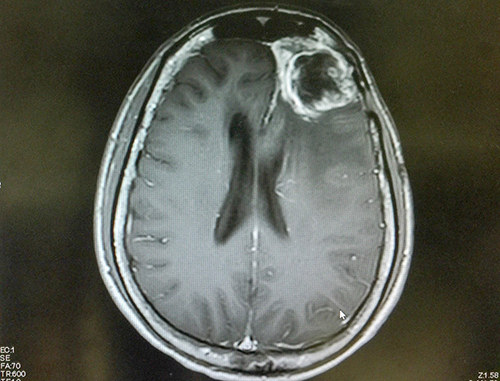

Also called glioblastoma multiforme, GBM, or grade IV astrocytoma, glioblastoma currently has a survival rate of just 15 to 16 months. While it usually manifests in the frontal and temporal lobes, it can appear anywhere in the brain and even the spinal cord.

Glioblastoma tumors are notoriously difficult to treat. They grow very quickly, inject finger-like protrusions into surrounding healthy tissue and are composed of several different kinds of cells, some of which only respond to different drugs, if at all. Present forms of treatment include the surgical removal of as much of the tumor as possible, followed by radiation and chemotherapy. New technologies, including gene therapy and immunotherapy, hold promise for improved life expectancy, but are not yet in widespread use.